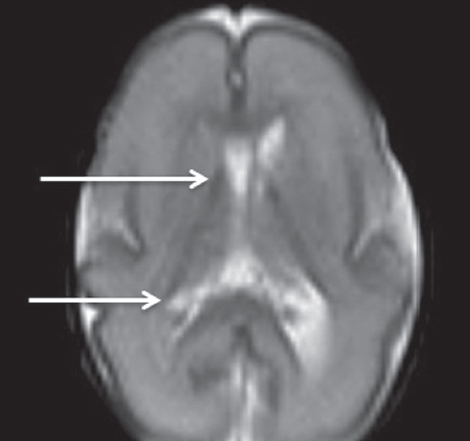

Patterns of neuroplasticity and cerebral maturation in preterm neonate can be assessed by MRI and cranial ultrasound. The score system of brain maturation includes the account of germinal matrix (GM) regression by MRI. The GM regression can be considered as pattern of neuroplasticity. There have been investigated the changes of neuroplasticity pattern or GM regression in preterm neonates with extremely low birth weight (ELBW) without intragerminal/intraventricular hemorrhages (n = 21). It is believe that the main causes of impair of GM are the intragerminal hemorrhages and hypoxia. The methods of study were cranial ultrasound (CU) and MRI. The measurement of GM was carried out by CU in anterior horn of the lateral ventricles of neonates in the study group (25-29 weeks). It was detected the GM regression in preterm neonates with increasing age, and complete GM regression to 30 week. MRI has been performed in 15 neonates from the study group on 27-38 weeks age with using the common pulse sequences – T1 WI, T2 WI and Flair. GM was detected by MRI up to 34 weeks inclusive by using the additional pulse sequence – DWI. By using common pulse sequences the GM was visualized up to 32 weeks age. Furthermore there has been pathological examination of GM in anterior horn of lateral ventricle in dead neonates from the study group (n = 3). We revealed the thickness reduction of GM in the lateral ventricles with increasing age of the dead neonates. Also we identified the delay of the GM reduction in two dead neonates 36-38 weeks age (post conceptual age) what may indicate the disorder of neuroplasticity in those preterm neonates. The performed study showed the capability of CU and MRI in examination of neuroplasticity in preterm neonates.